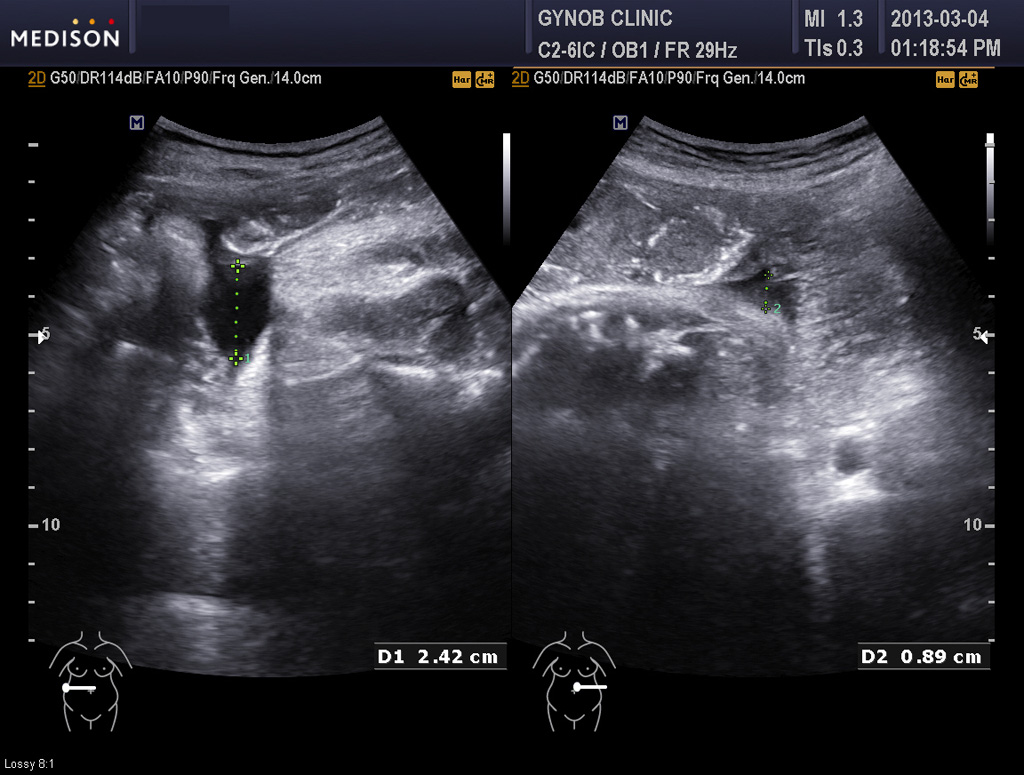

한분은 먼저 진찰에서도 조금 그렇기는 했지만 며칠 전 초음파 검사에서 양수양이 상당히 적은 양수 과소증(양수 점수인 AFI가  5점이하 수준)으로 판단되어 아기의 건강이 다소 위협 받고 있는 상황일 가능성이 있어서 이송한 경우였습니다.

다행히 아기 발육은 괜찮은 편이었지만 양수의 양은 아기의 건강을 나타내주는 지표 중의 하나이기도 하고 또 양수가 적으면 진통 중 탯줄이 눌리거나 하여 태아 곤란증에 빠지기도 해서 양수양이 너무 적은 것은 그리 좋은 신호는 아닙니다.

그런데 그 산모는 초음파 검사상 태아의 방광이 수시간 동안이나 비워지지 않고 꽉 찬 상태로 보여 혹시 태아의 비뇨기 계통의 기형인 "요관 말단 판막 (posterior urethral valve)"이라고 하는 기형이 있지 않은가 하는 의심이 들었습니다.

요관 말단 판막은 그리 흔한 기형은 아니지만 남자 아기에게서 주로 생기고 방광의 소변이 원활하게 체외로 나오지 못하는 기형입니다.

따라서 그런 기형이 있을 경우 방광은 많이 커지고 양수는 줄어들게 됩니다.

콩팥도 영향을 받는 경우가 많은데 그 산모의 태아는 콩팥은 이상이 없어 보였지만 경미한 타입의 판막증에서는 그럴 수도 있기 때문에 태아의 건강을 생각하여 산모와 상의하여 대학 병원에서 출산하기로 결정을 하였습니다.

아래 사진은 그 산모분의 산전 진찰시 초음파 사진인데 위는 양소 과소증을 나타내 주는 사진이고 아래는 태아 방광의 사진입니다.